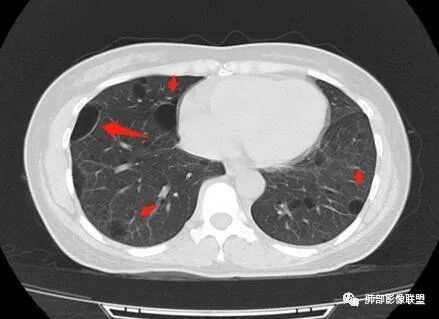

女,38岁,无症状,胸片体检发现两肺可疑病灶。

?其母亲有肺大泡,2017年手术。影像学特点:两肺胸膜下多发的大小不等囊状气腔,壁很薄或无可见的囊壁,小囊的边界比较清楚,大囊的形态比较怪异,以两下肺为著。考虑肺组织细胞增生症,鉴别肺淋巴管肌瘤病。

小叶中心,胸膜下囊,比较大,规则:

无其他伴随征象

常规:1、LAM 2、bhd

LAM?年龄、性别符合,囊形态符合,但是这么大囊的好像不多见,而且分布区域下肺为主的不多,没有结节,不是首选,但是不能排除

Birt-Hogg-Dubé综合征:影像符合,家族史符合